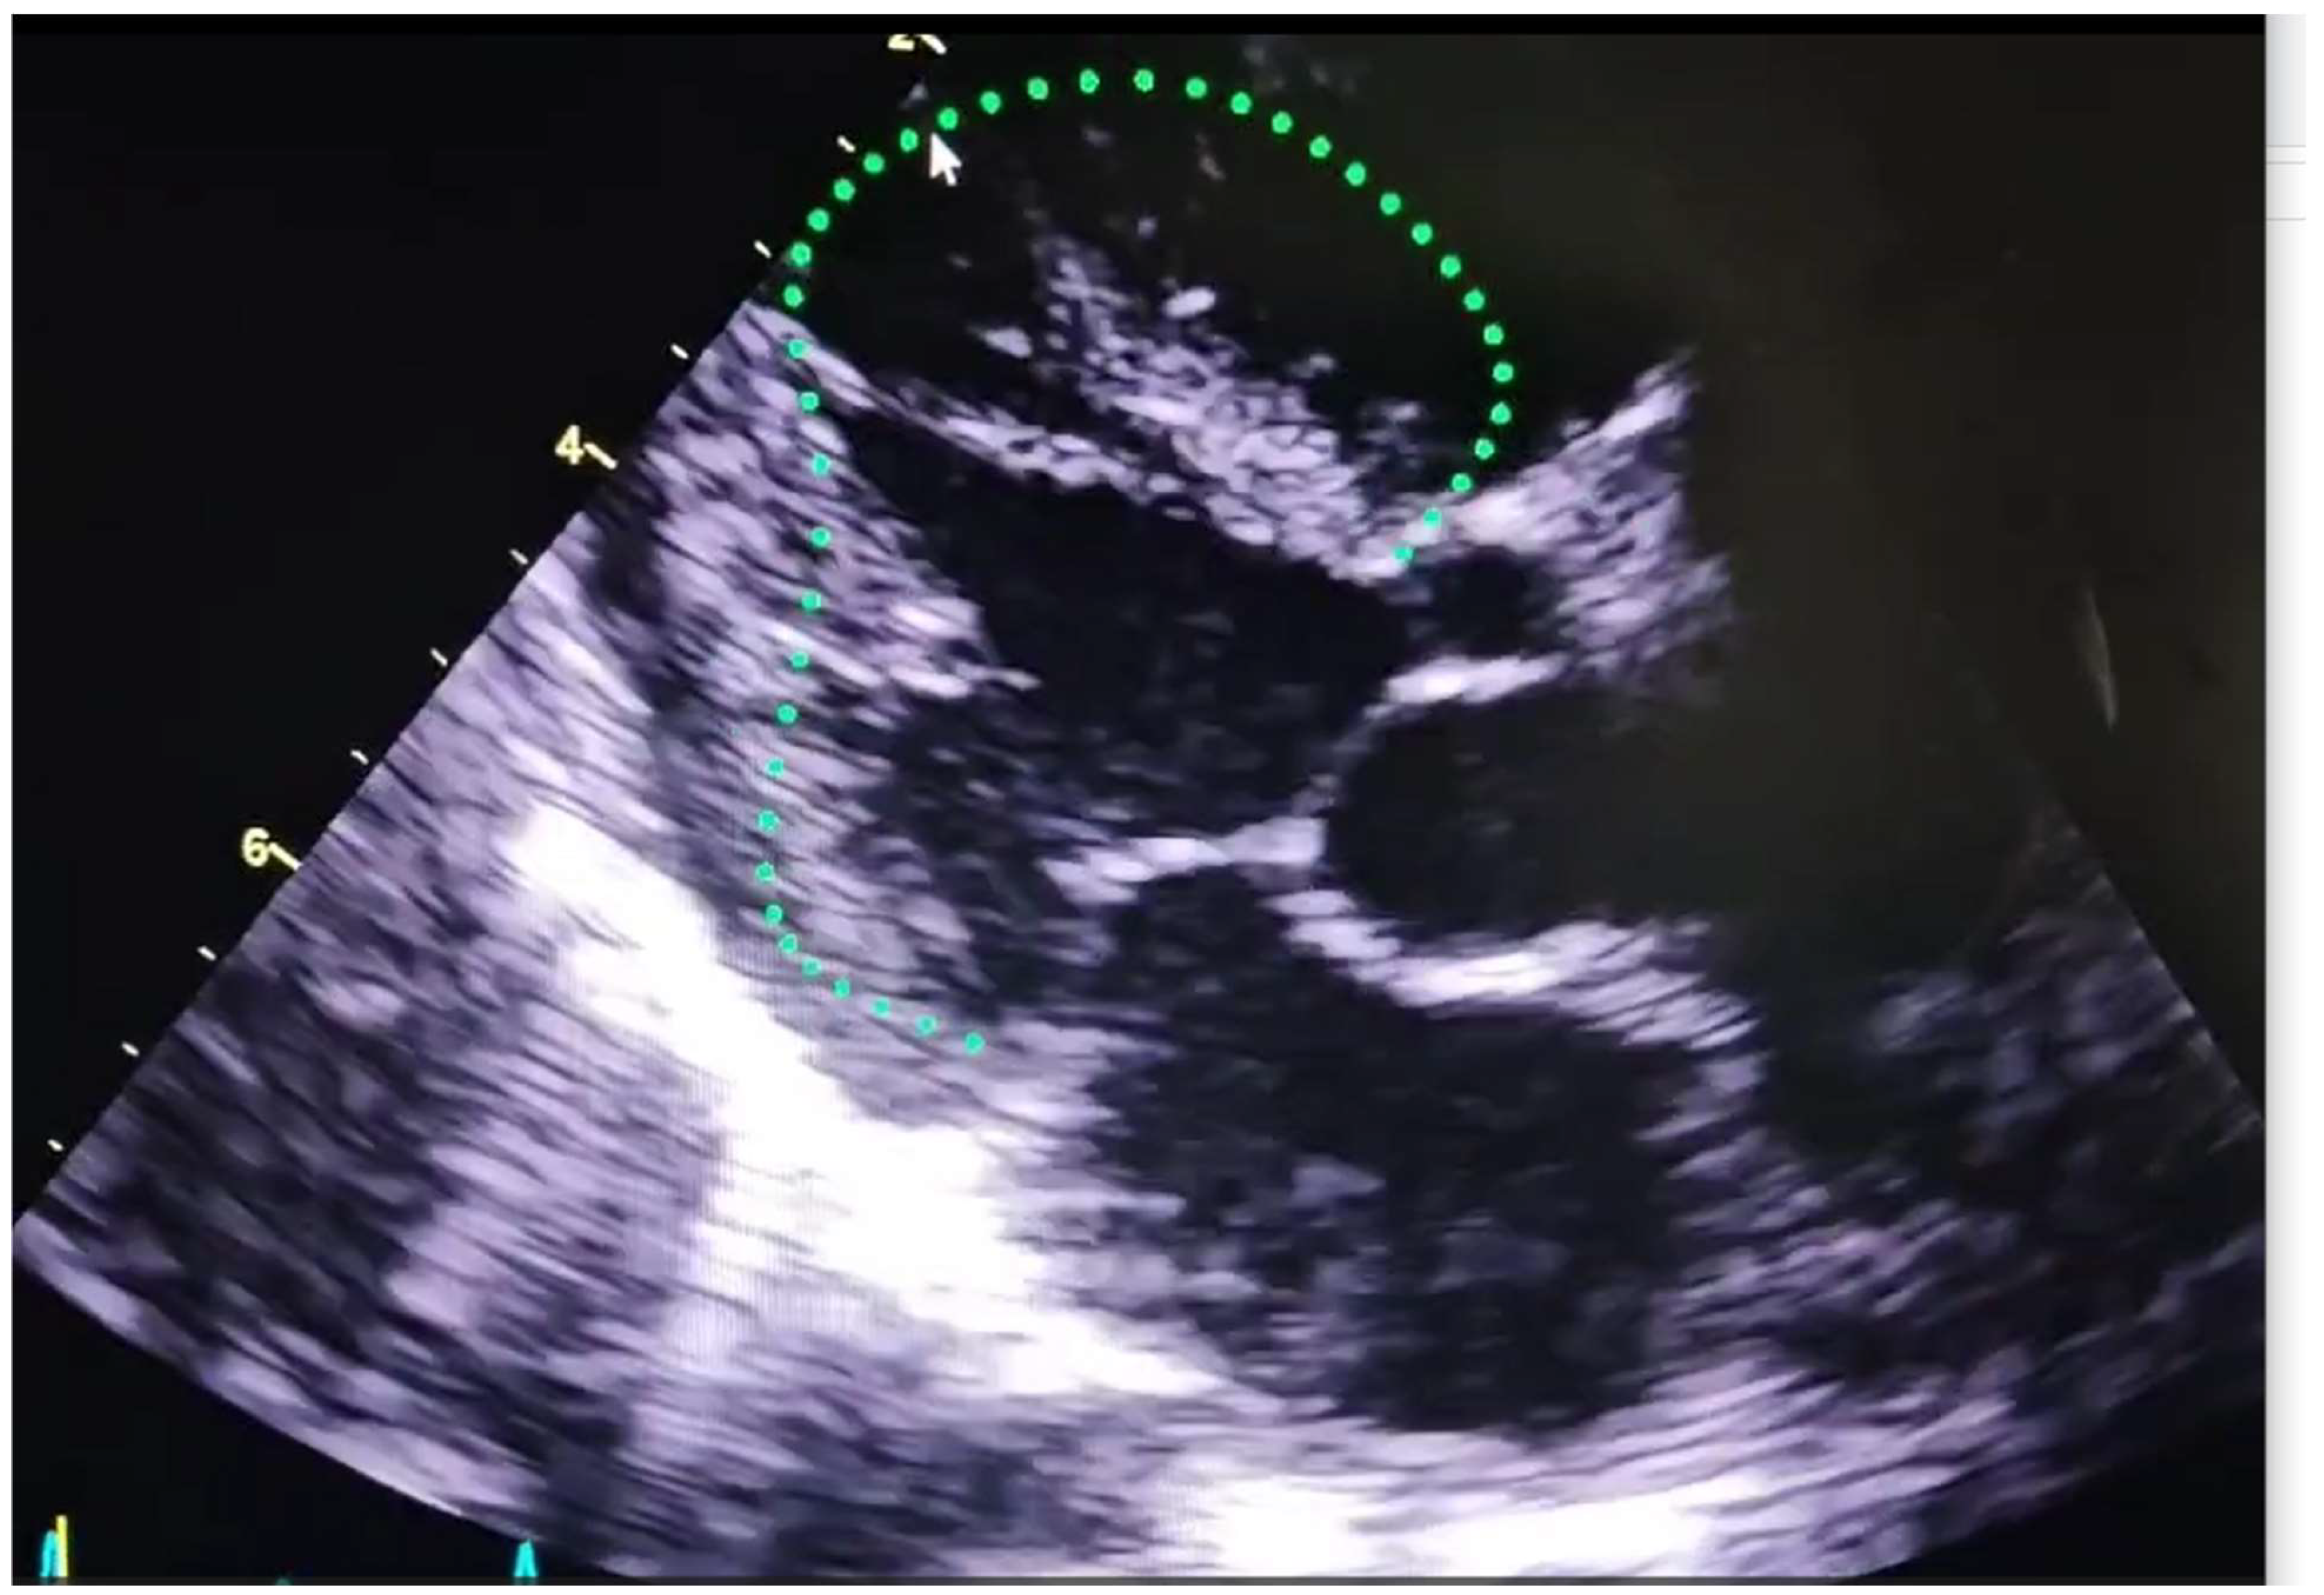

Challenges of Ai in echocardiography of complex congenital heart disease